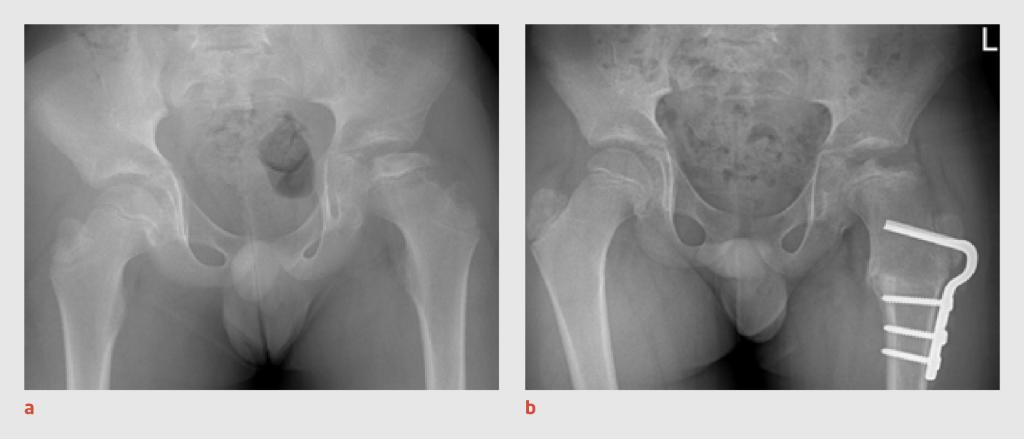

2 weken later bezocht patiënt opnieuw de huisarts, omdat de pijn in het bovenbeen toenam en zich uitbreidde naar de linker heup. Vanwege de aanhoudende pijn en de toename van de klachten verwees de huisarts patiënt door naar de spoedpoli Kinderorthopedie. Aldaar toonde het bloedonderzoek een licht verhoogde bezinking (33 mm na 1 h), zonder verhoging van de overige infectieparameters. Conventionele röntgenopnames van het bekken en het linker bovenbeen lieten geen afwijkingen zien. Wij vermoedden een subacute artritis of osteomyelitis en verrichtten aanvullend een MRI-scan van het bovenbeen en de heup, waarop in het linker proximale femur T2-hyperintense afwijkingen te zien waren, die passen bij een Brodie-abces met omringend beenmergoedeem in het kader van subacute osteomyelitis (figuur 1).

Subacute osteomyelitis bij een jongen van 8 jaar door een infectie met Kingella kingae

Figuur 1 | Subacute osteomyelitis bij een jongen van 8 jaar door een infectie met Kingella kingae

Coronale beelden van de MRI-scan van beide heupgewrichten laten T2-hyperintense afwijkingen zien in het linker proximale femur, die passen bij een Brodie-abces met omringend beenmergoedeem in het kader van subacute osteomyelitis.